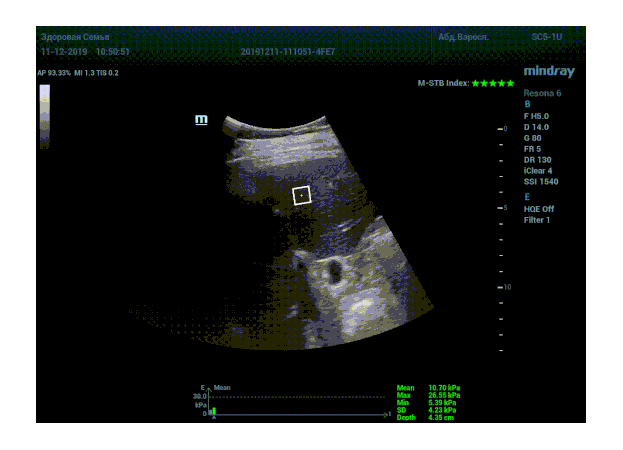

Определение плотности печени. Не ошибся ли оператор при измерении эластических свойств печени? Для оценки критериев качества предусмотрен индекс MBT, который покажет насколько «твердой» была рука оператора и двигалась ли печень. При MBT 5* рука тверда и показатели достоверны. Для оценки качества результатов используется IQR индекс, отображающий колебания показателей в точке измерения при расчете медианы. Показатели при IQR <30% считаются приемлемыми. Техника сканирования через межреберные промежутки требует размещение окна интереса на несколько сантиметром ниже капсулы, для исключения эффекта реверберации. Установка ROI на паренхиму без захвата сосудов, для исключения погрешностей измерения.

Стадия фиброза определяется по системе METAVIR Staging, построенной на данных биопсии и сопоставлении с данными эластографии. Своевременная диагностика фиброза, и начало его лечения, залог благоприятного исхода заболевания.

• METAVIRF2 – Портальный фиброз с вовлечением нескольких перегородок